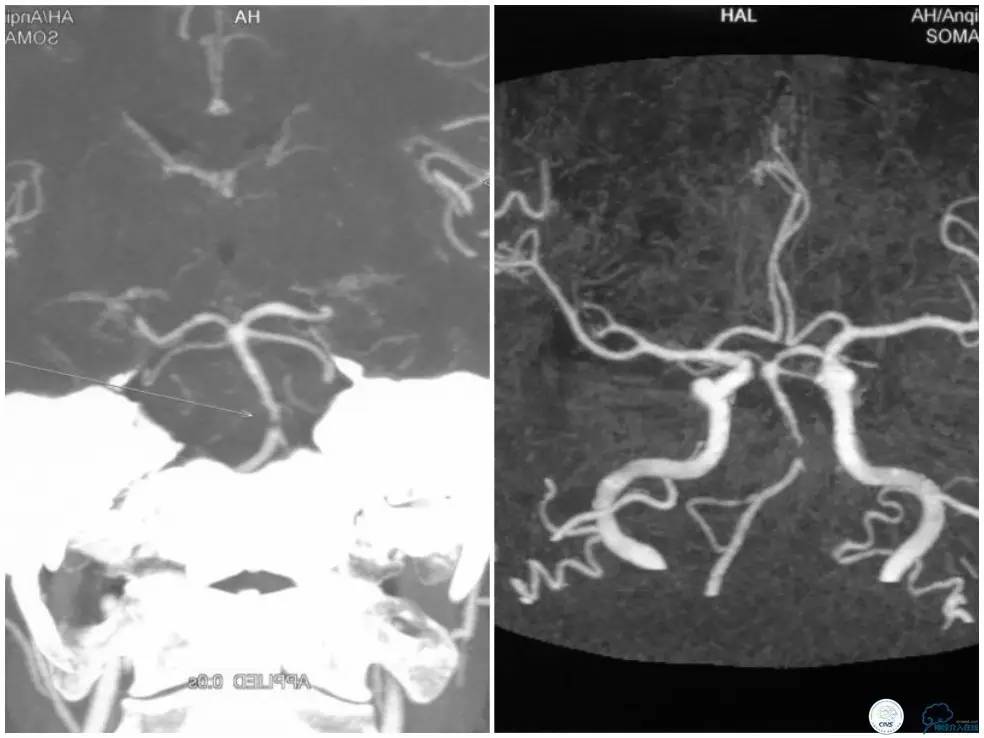

颅内动脉粥样硬化性狭窄多为偏心性狭窄分布于管腔某一壁。但我们也可见突出于管腔内的狭窄,造影显示狭窄轮廓不清,某些投造体位可见充盈缺损(图1,来自秦皇岛市第一医院,杨大为主任提供),类似“蜂巢样”改变,或者呈“夹层样”改变。本周我们汇报病例系一例基底动脉“蜂巢样”狭窄支架治疗的过程。

图1